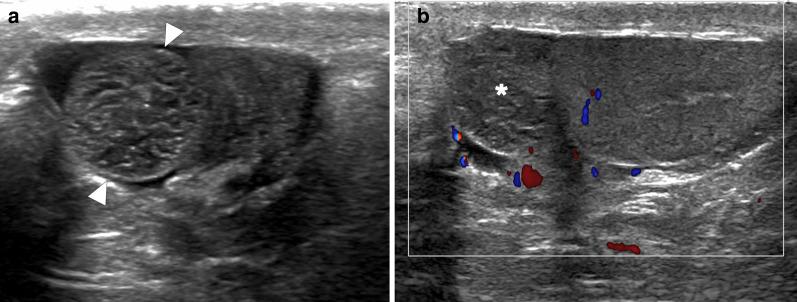

Identifying the deceiver: the non-neoplastic mimickers of genital system neoplasms.

Tumors of the genital system are common and imaging is of crucial importance for their detection and diagnosis. Several non-neoplastic diseases may mimic these tumors and differential diagnosis may be difficult in certain cases. Misdiagnosing non-neoplastic diseases as tumor may prompt unnecessary medical treatment or surgical interventions. In this article, we aimed to present the imaging characteristics of non-neoplastic diseases of the male and female genital systems that may mimic neoplastic processes. Increasing awareness of the imaging specialists to these entities may have a severe positive impact on the management of these patients.